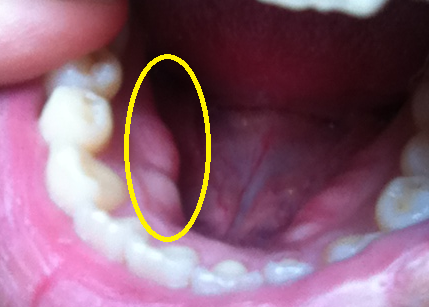

歯の内側に膨らみがある人は、よく歯を食いしばる人みたいです。

食いしばりすぎて歯で押された骨が出てきてる?

もし、口の内側に膨らみが有る人は「レジン」を奥歯に詰めない方が良いですよ~